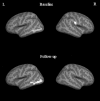

Magnetic resonance imaging data were acquired at ∼24 h and ∼3 months post-injury on mild traumatic brain injury (mTBI; n = 75) and orthopedic injury (n = 60) cohorts. The mTBI subjects were randomly assigned to a treatment group with atorvastatin or a non-treatment mTBI group. The treatment group was further divided into drug and placebo subgroups. FreeSurfer software package was used to compute cortical thickness based on the three dimensional T1-weighted images at both time-points. Cross-sectional analysis was carried out to compare cortical thickness between the mTBI and control groups. Longitudinal unbiased templates were generated for all subjects and cortical thickness measurements were compared between baseline and follow-up scans in the mTBI group. At baseline, significant reduction in cortical thickness was observed in the left middle temporal and the right superior parietal regions in the mTBI group, relative to the control group (p = 0.01). At follow-up, significant cortical thinning was again observed in the left middle temporal cortex in the mTBI group. Further analysis revealed significant cortical thinning only in the non-treatment group relative to the control group. In the follow-up, small regions with significant but subtle cortical thinning and thickening were seen in the frontal, temporal, and parietal lobes in the left hemisphere in the non-treatment group only. Our results indicate that cortical thickness could serve as a useful measure in identifying subtle changes in mTBI patients.